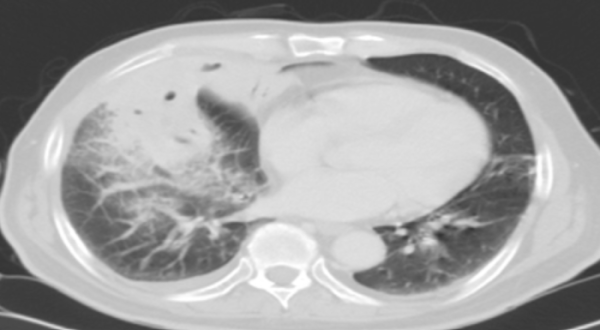

폐렴은 세균이나 바이러스의 감염으로 폐에 염증이 생기면서 발병한다. 폐포 내 미생물 균주가 증식하고 환자가 균주에 대한 면역반응을 일으키면서 폐와 전신에 염증반응이 생겨 가래, 기침, 발열 등의 증상이 나타난다. 폐렴균 중 가장 흔한 세균인 폐렴구균의 병원소는 무증상 보균자의 비인두다.

입안과 인후두 안 분비물은 수면 중 또는 무의식적으로 기도로 미세흡인될 수 있다. 이때 균이 분비물과 함께 기도로 들어가는 것이 가장 흔한 폐렴 감염 경로다. 인체의 다양한 방어작용에도 균이 폐의 안쪽까지 들어와 폐포까지 들어오고 균이 증식되면, 주변에 있는 염증 세포들이 모여 염증 반응이 시작된다. 염증반응의 부산물로 발열이나 가래(객담) 같은 폐렴의 임상증상이 나타난다.